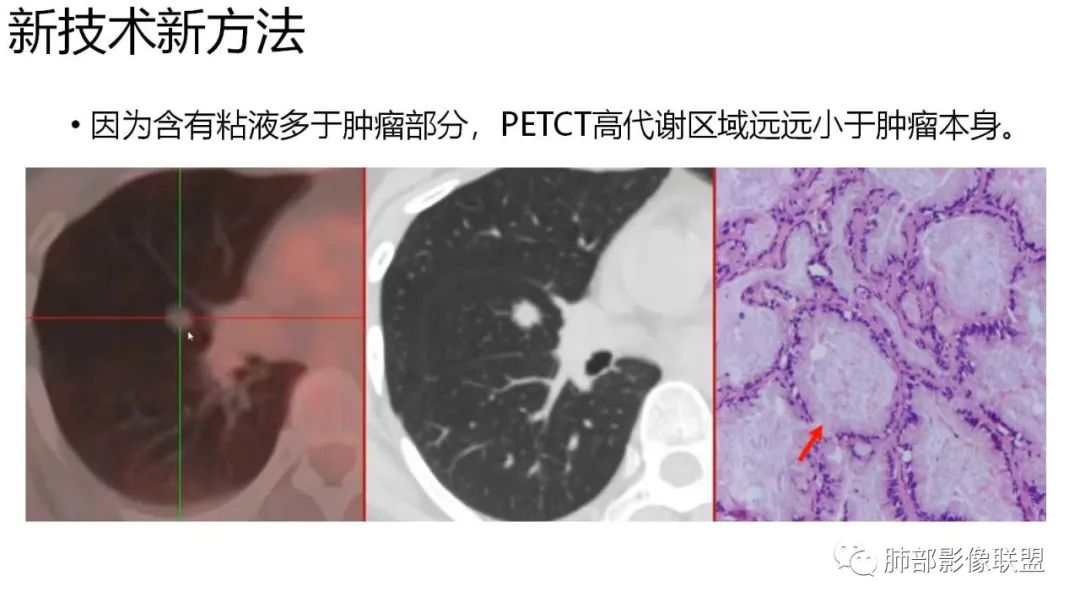

4、增强后不均匀强化,存在低强化区呈弱强化或无强化,因此可见“血管造影征。”血管毛糙与肺炎有统计学差异。

9.粘液腺癌的变化规律:结节缓慢发展而来,向周围播散形成斑片后可快速进展,有时支气管镜后或粘液排出后局部可形成好转的假象。病灶可沿肺泡和支气管播散。